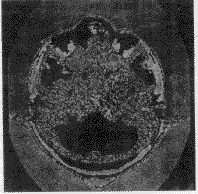

2.4 结果显示

对手术方案的结果进行三维显示和多剖面显示是可视化的关键。系统考虑到各种显示方法的优缺点,对它们进行合理的运用和改进。对医生勾画的重要功能区采用面向多边形的表面显示算法,重建出的区域立体感强,图7是对医生勾画的眼球、视神经和脑干的重建结果。对于颅骨的显示,系统采用了直接投影的体显示法和改进的Marching Cube算法两种,后一种算法可弥补前一种算法对光照效果的过分依赖,而前一种算法则可弥补后一种算法过长的前处理时间的不足,供医生依情况选择,图8、图9为两种算法的显示结果。对于外皮肤的显示,系统综合利用面向多边形的显示方法和面向体素的表面显示方法,首先将构成外皮肤的所有像素自动提取出来,然后利用面向多边形的表面显示方法形成外皮肤,显示的图像比采用Marching Cube算法显示的更细腻、平滑,图10为显示结果。图11为一个复合显示结果。

图 8 直接投影的颅骨显示

图 9 改进MC的颅骨显示